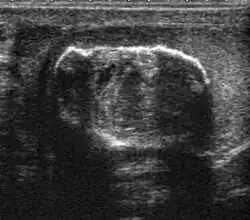

Fig. 29. Undescended testis. (a) Normal testis in the scrotum. (b) Atrophic and decreased echogenicity of the contralateral testis of the same patient seen in the inguinal region.